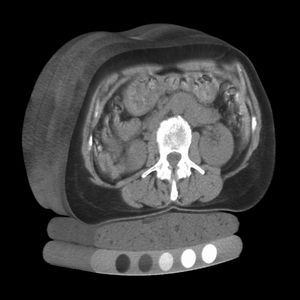

단층촬영술은 물체의 내부 구조를 다양한 물리 현상을 이용하여 영상으로 재구성하는 기술을 의미한다. 영상 재구성은 해석적, 대수적, 통계적 방법으로 분류되며, 필터 보정 역투영법(FBP)과 반복 근사 영상 재구성법(IR)이 주로 사용된다. 단층 촬영은 라돈 변환을 기반으로 하며, 평행 빔, 부채꼴 빔, 원뿔 빔 등 다양한 광학계를 사용한다. X선, 중성자, 뮤온, 지진파, 음파 등 다양한 데이터 소스를 활용하여 여러 종류의 단층 촬영 기술이 존재하며, 최근에는 여러 기술을 통합하여 사용하기도 한다. 볼륨 렌더링은 3차원 데이터 세트의 2차원 투영을 표시하는 데 사용되는 기술이며, 초점면 단층 촬영술은 1930년대에 개발되어 1970년대 후반 컴퓨터 단층 촬영술에 의해 대체되었다. 싱크로트론 X선 단층 현미경(SRXTM)은 화석 등 3차원 스캔에 사용되는 기술이다.

| X선 단층 촬영 (CT) | X선을 사용하여 인체 내부의 단면 이미지를 얻는 기술 |

단층 촬영은 물체를 파괴하지 않고 내부 구조를 시각화하기 위해 다양한 물리적 원리를 활용한다. 대표적으로 X선을 이용하는 CT, 자기 공명 현상을 이용하는 MRI, 초음파를 이용하는 기법 등이 널리 사용된다. 이 외에도 감마선, 중성자, 뮤온과 같은 입자나 전기 용량, 전기 저항, 빛, 음파 등 다양한 물리 현상을 데이터 소스로 활용하는 여러 종류의 단층 촬영 기술이 개발되어 의학, 산업, 과학 연구 등 다양한 분야에서 응용되고 있다.[2][3][4][5][6][7][8][9][10][11][12][13][14][15]